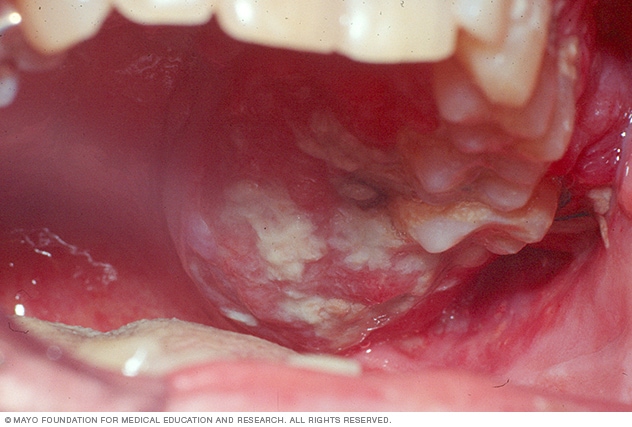

Mundkrebs – weiße Flecken

Anzeichen von Mundkrebs können Blutungen, Schwellungen, weiße Flecken oder Rötungen im Mund sein.